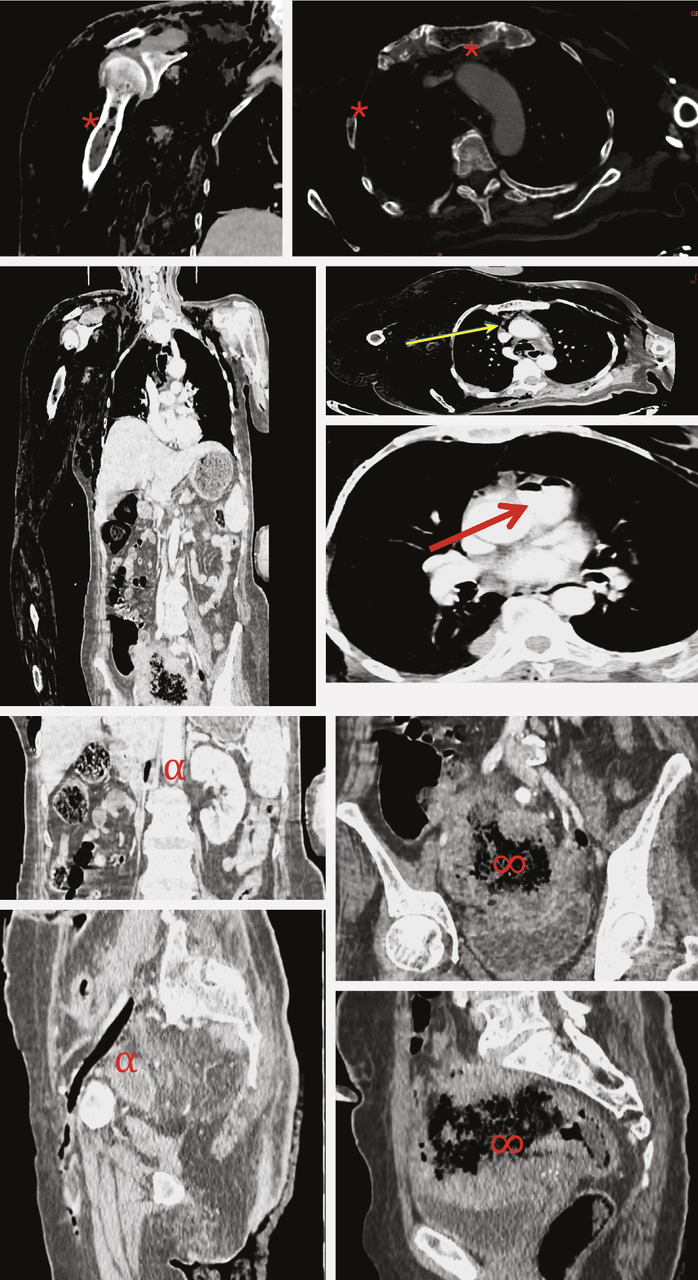

Une femme de 70 ans, diabétique, suivie pour un cancer du côlon depuis un an et demi, sous chimiothérapie, se plaint, depuis la veille de son admission aux urgences, de douleurs intenses au niveau du membre supérieur droit avec apparition de phlyctènes (fig. 1 ) ainsi qu’au niveau des jambes (fig. 2 ) et du torse. Cliniquement, la patiente est confuse, hypotendue, avec à la palpation des crépitations au niveau cervico-thoracique et au niveau du membre supérieur droit. Le bilan infectieux est positif, avec des globules blancs à 20 000/mm3 et une protéine C-réactive (CRP) à 432 mg/L. Un scanner cervico-thoraco-abdomino-pelvien et des membres avec injection est réalisé. Il montre un important emphysème disséquant des parties molles cutanées, sous-cutanées et musculaires des parois cervico-thoraco-abdominales ainsi que des deux membres supérieurs et du membre inférieur gauche, associé à un pneumomédiastin de moyenne abondance, une aéroportie, quelques bulles d’air au niveau du tronc des artères pulmonaires, de la veine cave inférieure, des veines iliaques commune et externe gauches et des veines fémorales homolatérales et en intra-osseux au niveau sternal, de la clavicule, de l’omoplate, des quatre premières côtes et de l’humérus droits (fig. 3 ). Le scanner montre également une embolie pulmonaire segmentaire lobaire moyenne et une occlusion totale de l’artère axillaire droite, sans reprise d’aval, ainsi que le processus tumoral sigmoïdien localement avancé déjà connu. Après parage des lésions du membre supérieur droit et inférieur gauche, la patiente est hospitalisée en unité de soins intensifs. L’hémoculture révèle la présence de Clostridium septicum. La patiente décède malheureusement seize heures après son admission.

La gangrène gazeuse se définit par une nécrose tissulaire avec production de gaz quel que soit le tissu atteint ou les germes anaérobies en cause. Il s’agit d’une affection grave, aboutissant inévitablement au décès du patient en l’absence de prise en charge rapide et adéquate.1 Elle survient généralement à la suite d’une plaie ou d’une chirurgie. Plus rarement, elle peut survenir dans un contexte atraumatique. Dans 80 % des cas, on retrouve une pathologie tumorale sous-jacente intéressant principalement le tube digestif, avec une nette prédominance des tumeurs coliques.2 Il a été prouvé, dans la littérature, qu’il existe une relation entre ces dernières et la bactériémie à Clostridium septicum. En effet, il s’agit d’une bactérie à Gram+, anaérobie et sporulée qui se multiplie dans un milieu acide et hypoxique induit par la tumeur et qui pénètre dans le sang à travers des altérations épithéliales provoquées également par le cancer,3 occasionnant une septicémie fulminante.4 Le scanner cervico-thoraco-abdominal est l’examen clé permettant d’orienter le diagnostic étiologique, d’apprécier l’extension des fusées gazeuses souvent inaccessibles à l’examen clinique et d’adapter ainsi le traitement chirurgical et de surveiller les lésions.1 La prise en charge thérapeutique doit être rapide ; elle consiste en un débridement chirurgical et un traitement médical adapté en unité de soins intensifs.